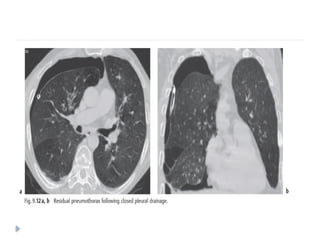

PNEUMOTHORAX

 Pneumothorax is defined as a collection of air in the pleural

cavity

 is divided into spontaneous and traumatic types

Radiologic features

 As with pleural effusion, the radiographic appearance of

pneumothorax depends on the radiographic projection, the

patient’s position, and the presence or absence of pleural

adhesion and subsequent loculation.

 Plain radiograph

 usually easily appreciated on erect chest radiographs.

 Typically they demonstrate:

 visible visceral pleural edge is seen as a very thin, sharp white

line

 no lung markings are seen peripheral to this line

 peripheral space is radiolucent compared to the adjacent lung

 lung may completely collapse

 mediastinum should not shift away from the pneumothorax

unless a tension pneumothorax is present

 CT

 Provided lung windows are examined, a

pneumothorax is very easily identified on CT, and

should pose essentially no diagnostic difficulty.

 pneumothorax is imaged as air in the pleural

space outside the lung and visceral pleura.

 Even a very small pneumothorax is visible in the

anterior pleural space.

 Its diagnosis is usually straightforward, although

differentiating a medial pneumothorax from

pneumomediastinun may be difficult in some

cases.